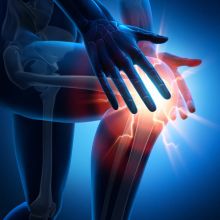

Bolesti kolenního kloubu